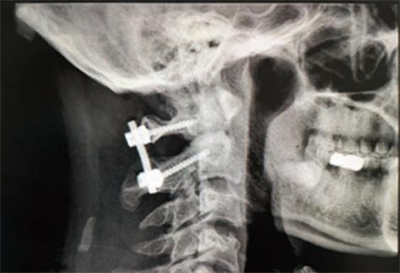

术后效果

术后第二天,患者即可下床活动,复查显示寰枢关节位置关系良好。“手术后颈痛和双手麻木感消失了,没有什么不适的感觉”,患者满意地说道。